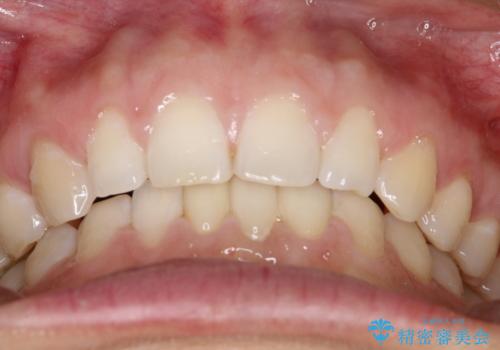

【空隙歯列】ワイヤー矯正で短期間に治療を終えたい

- 歯と歯の間に隙間があることを主訴に来院されました。

短期間での治療終了を希望され、ワイヤー矯正にて治療を行い1年ほどで治療を終了しております。

下顎前歯は矯正後補綴治療を行なっております。